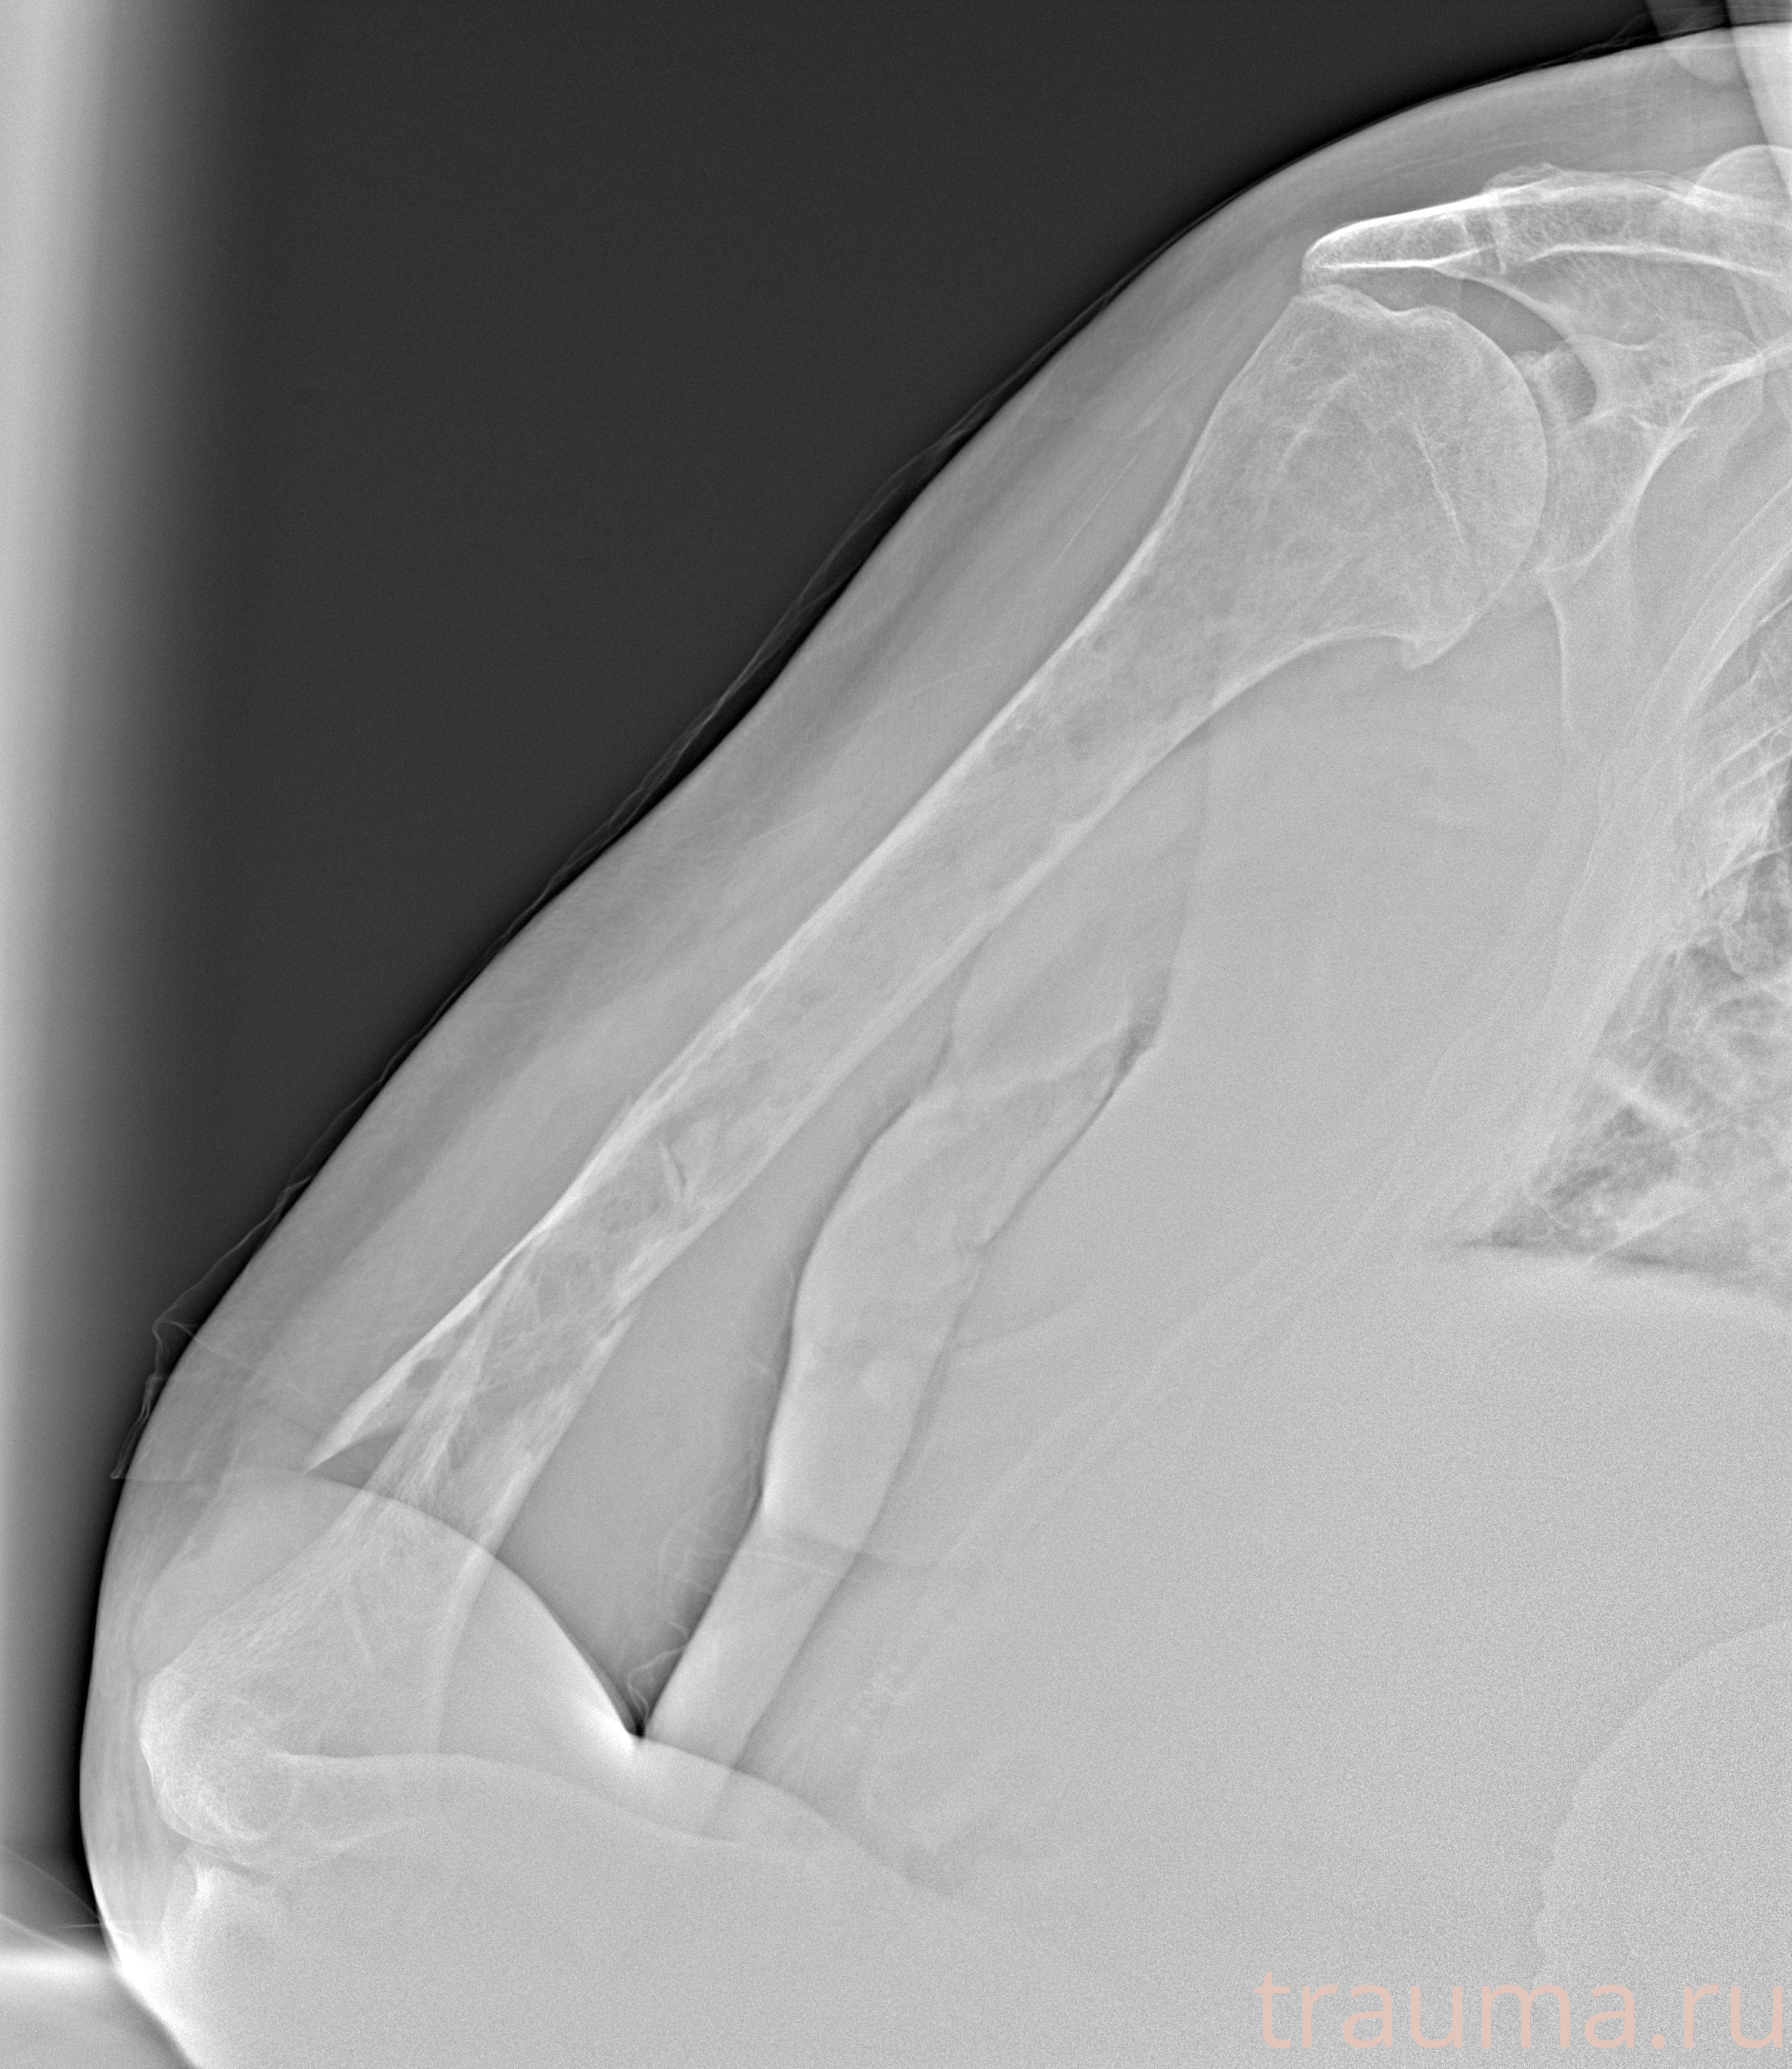

Рентген на дому: по вашему адресу приезжает врач-рентгенолог, травматолог-ортопед с мобильным рентгеновским аппаратом, проводит диагностику травмы или заболевания, делает необходимые рентгенограммы, дает рекомендации по дальнейшему лечению. Получить качественные снимки в домашних условиях возможно благодаря уникальной методике, разработанной МосРентген Центром для института  Склифосовского